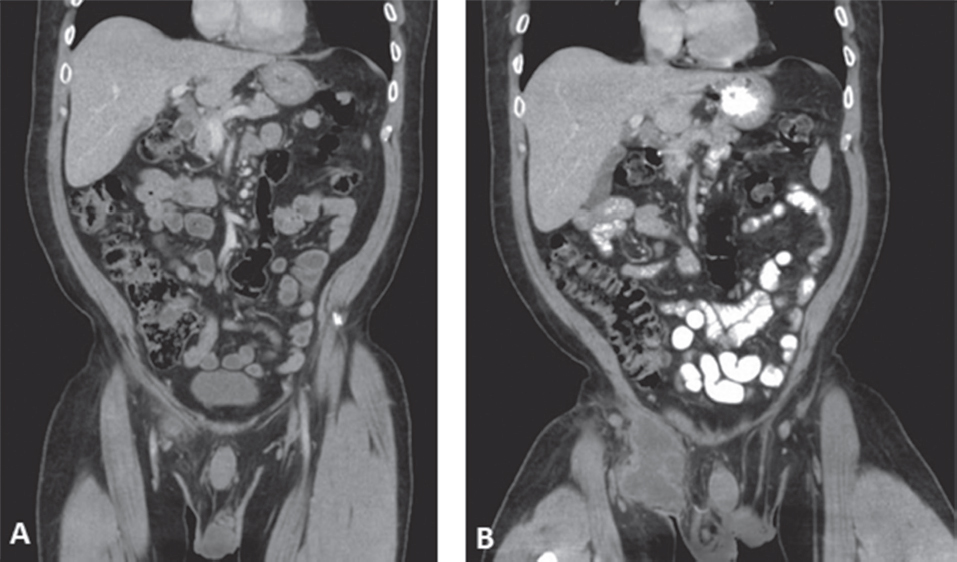

Gordon ma, banda ht, gondwe m, et al. It can be difficult to believe that your favorite food can cause you to become sick Focal salmonella infection can occur with or without sustained bacteremia, causing pain in or referred from the involved organ—the gastrointestinal tract (liver, gallbladder, appendix), endothelial surfaces (eg, atherosclerotic plaques, ileofemoral or aortic aneurysms, heart valves), pericardium, meninges, lungs, joints, bones, genitourinary tract, or soft tissues. When salmonella infections become invasive, they can affect the bloodstream, bone, joint, brain, or nervous system, or other internal organs. Nontyphoidal salmonella are important foodborne pathogens that cause gastroenteritis, bacteremia, and subsequent focal infection.

Focal salmonella infection can occur with or without sustained bacteremia, causing pain in or referred from the involved organ—the gastrointestinal tract (liver, gallbladder, appendix), endothelial surfaces (eg, atherosclerotic plaques, ileofemoral or aortic aneurysms, heart valves), pericardium, meninges, lungs, joints, bones, genitourinary tract, or soft tissues.